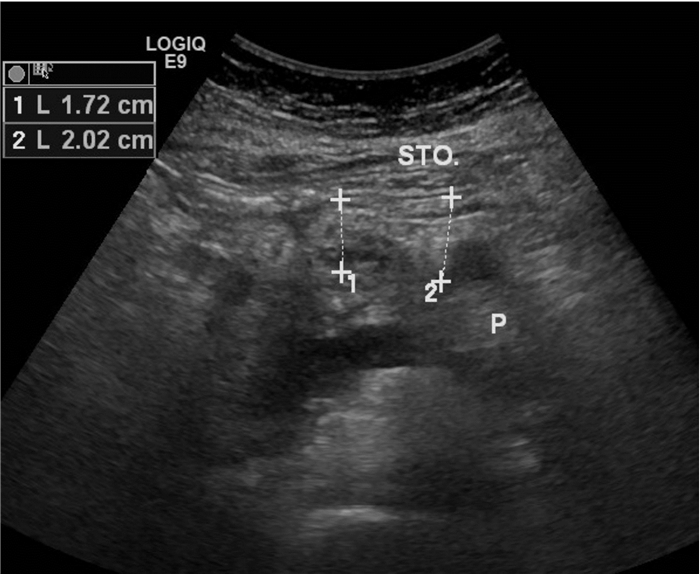

1.4 小网膜囊增厚超声判断标准:正常情况下,小网膜囊超声不显示(图 1),以胰胃间距增加作为小网膜囊增厚的判断标准。

| 上排箭头:胃后壁,其浆膜面构成网膜囊前壁;下排箭头:胰腺前缘,构成网膜囊后壁;STO:胃;P:胰腺 图 1 正常情况小网膜囊超声图示 |